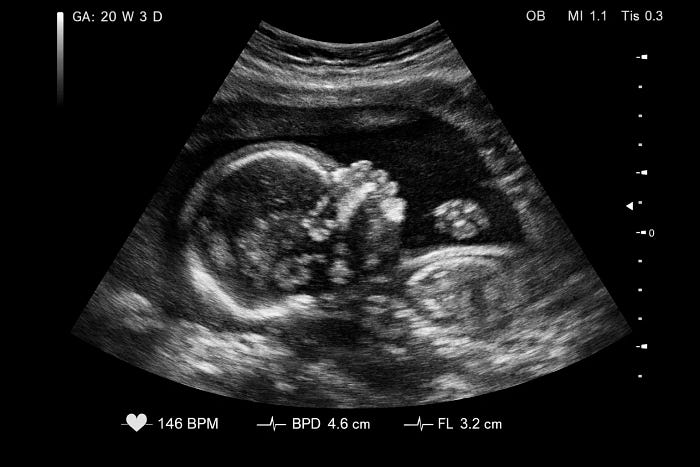

3. Morphology (Anatomy) Scan (18–22 Weeks)

Right from the initial months, all expecting mothers wait with bated breath to see that first glimpse of their babies. A tiny yawn, or a thumb tucked into a mouth, or whatever signs of life they can see are precious moments. And a morphology scan, done at the 18–22 week marker, can give you such sure signs of the baby’s warm and solid presence. In this scan, our sonographers examine the following:

● A thorough anatomical check, including the heart, brain, spine, and vital organs, to ensure everything is forming correctly.

● Assessing the position of the placenta and the levels of amniotic fluid that support your baby.

● Taking precise measurements to ensure your baby is growing at a healthy and consistent rate.

This is also the point where most couples prefer to go for a Gender Scan, which you can take anytime after 17 weeks into the pregnancy. It is a safe and accurate way of finding out whether you’re having a boy or a girl.

Morphology scan is complex and detailed, and hence, requires a referral. It is a cornerstone of your prenatal care, providing your doctor with the data they need to support a healthy second half of your pregnancy.